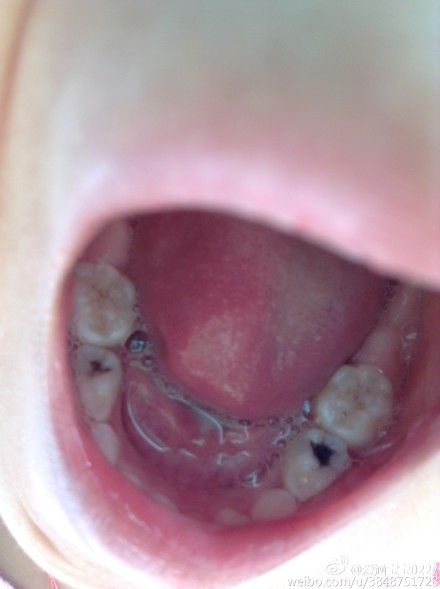

@用户:孩子两岁八个月,牙齿变黑了,去诊所问了下说是要从牙齿上钻眼然后放上药,觉得特别恐惧,该怎样正确治疗和护理呢?望你回复

儿童牙医朱涛:看上去像是蛀牙,但只凭看还不能诊断。蛀牙根据轻重治疗方法不同,若不涉及牙髓,去腐充填即可,若累及牙髓治疗比较复杂,建议去比较好医院或诊所检查治疗。